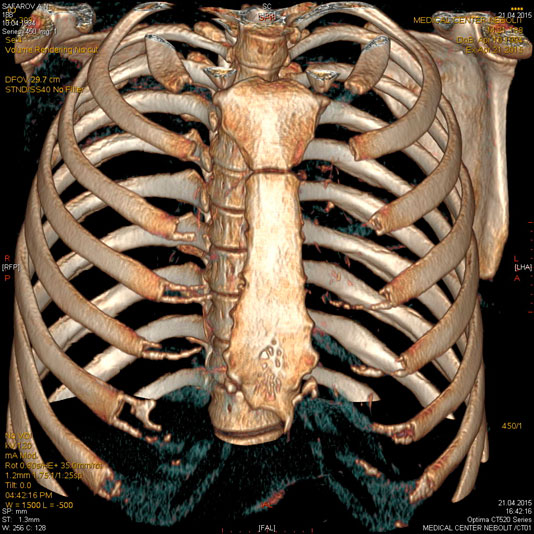

МСКТ органов грудной клетки (легких и средостения).Рентген является базовым методом исследования грудной клетки. МСКТ применяется в выявлении стадии рака легкого, туберкулеза, определяет структуру патологических образований, таких как киста, солидный компонент, сосудистые, жидкостные и воздушные полости, подозрение на ТЭЛА.

С появлением МСКТ уходит в прошлое КТ с высоким разрешением для диагностики интерстициальных заболеваний легких. При использовании МСКТ можно дифференцировать диффузные интерстициальные процессы в легких альвеолит, бронхиолит, саркоидоз, канцироматоз и очаговые изменения.

Астма и хронический бронхит диагностируются клинически. Половина больных с хроническим бронхитом имеют нормальную картину при рентгенографии. При МСКТ у пациентов можно выявить признаки обструкции-участки вздутия легочной ткани обусловленные закупоркой мелких бронхов, участки гиповентиляции за счет отека слизистой, эмфизематозные буллы, дисковидные ателектазы, бронхоэктазы.

Показания:

- Выявление изменений в легких не отображающихся на рентгенограммах

- подозрение на объемное образование легких, средостения, плевры, диафрагмы,

- лимфоаденопатия неясного генеза,

- синдром долевых и сегментарных затемнений, когда обычного рентгенологического исследования недостаточно для постановки диагноза

- для уточнения наличия очагов отсева или полостей распада при специфических поражениях легких и средостения

- аномалии развития бронхо — легочной системы

- воспалительные заболевания легких и средостения, осложнения пневмонии

- детализация диффузных изменений

- подозрение на разрыв расслоение аорты, хроническую эмболическую легочную гипертензию

- травма

- медиастинит

- опухоли пищевода

Предварительное рекомендуемое обследование: рентгенография грудной клетки

Подготовка:Не требуется.

Эмболии лкгочной артерии, источником которых обычно являются тромбы в венах таза и нижних конечностей являются грозным и относительно частым осложнением особенно у лежачих больных и после операции. Данные при рентгенографии неспецифичны. Без инфаркта может определяться приподнятие купола диафрагмы и сужение теней сосудов к периферии. Возможности МСКТ в диагностике ТЭЛА в ряде случаев позволяют отказаться от проведения инвазивной ангиографии.